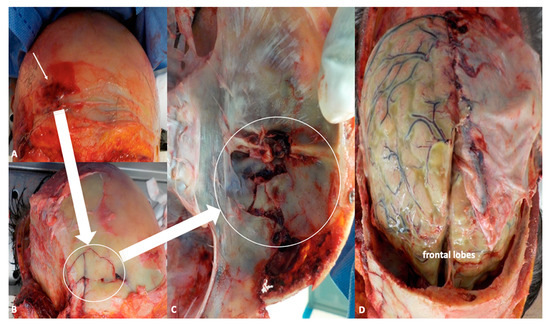

In recent years, the incidence and morbidity of meningitis have been decreasing thanks to widespread vaccination programs, timely diagnosis, and more effective treatments. Nevertheless, this condition still represents a heavy burden, in terms of both global health and expenditures, with an estimated 2.82 million cases in 2016, the highest toll being paid in the so-called “meningitis belt”, including peri-Sahelian countries of sub-Saharan Africa [1]. In high-income areas, such as the United States and Western Europe, annual incidence is about 1–3 cases/100,000 people [6]. The above-mentioned public health policies have also produced remarkable changes in the distribution and prevalence of microbial agents commonly underlying the development of meningitis. More specifically, the number of cases related to Haemophilus influenzae type b and Neisseria meningitidis (which is responsible for seasonal outbreaks, especially affecting young adults) have dramatically dropped thanks to the introduction of conjugate vaccines, so that nowadays, Streptococcus pneumoniae is by far the most common causative organism of community-acquired meningitis among immunocompetent subjects [6], particularly adults over 50 years of age and children under 2. Apart from age-specificity, well-known risk factors for pneumococcal meningitis are immunocompromised states, either congenital (mainly defects of innate immunity) or acquired, such as diabetes, alcoholism, human immunodeficiency virus (HIV), cancer, splenectomy, and immunosuppressant medications [7]. Another common cause of meningitis in immunodeficient and elderly patients is Listeria monocytogenes, which is the third most frequent pathogen in adult cases of meningitis, after S. pneumoniae and meningococcus serogroup B [8]. Along with immunological factors, anatomical defects also represent a crucial predisposing condition for intracranial infections, as they produce a breach in the complex defense systems (e.g., skull, cerebrospinal fluid (CSF) spaces, blood–brain barrier, CSF–brain barrier) aimed to guarantee central nervous system (CNS) integrity and homeostasis. TBI, mainly owing to motor vehicle accidents and falls, is the leading cause of acquired anatomical defects, with an incidence of meningitis following moderate-to-severe head trauma estimated to be around 1.4% [9]. Among adults (6.2–12.14%) with trauma-related skull fractures, 20% present with fractures of the skull base, more frequently involving the anterior cerebral fossa (ACF) (47%), followed by middle fossa (22–37%), and posterior one (0.21–3%) (Figure 2 A–D) [10].

Figure 2.

(A,B) Autoptical findings: exposure of the skull by facial skin overturning. This technique allows to evaluate the periorbital region as well as zygomatic and nasal bones (white arrow indicates fractures of the frontal region). (C) Fractures of the anterior fossa are easily detectable after removal of the brain (white arrow), while inspecting the basal skull. (D) In situ inspection of the brain. The leptomeninges shows frank green color owing to the presence of purulent material stratified under the meninges.

Basilar skull fractures are associated with higher risk of CSF leak, which occurs in 12–30% of these cases (compared with 2% of all head traumas), especially if ACF structures are damaged, where both bone and dura are thinner, and the latter is more adherent to the skull [11]. CSF leak is an ominous sign, as it depends on the presence of a direct communication between subarachnoid space and external environment, and thus facilitates the penetration of microbial agents (e.g., resident flora in nasopharyngeal mucosa), which might be responsible for meningitis and other intracranial infections. CSF leak may appear as rhinorrhea or, less frequently, as otorrhea, and is more commonly observed in frontal and sphenoid sinus involvement (30%), followed by ethmoid (15–19%) and cribriform plate (7.7%) fractures. Rhinorrhea and/or otorrhea might occur immediately after the trauma or be delayed, or even present as low-volume, intermittent discharges, which makes them difficult to detect. Although CSF leaks tend to resolve spontaneously after TBI, they might persist over days, increasing the risk of developing meningitis, especially when exceeding one week [12]. In cases of traumatic CSF fistulas, the rate of meningeal infection is about 9.1% in the first week, when the patient is generally hospitalized—so that a diagnosis of “nosocomial meningitis” is to be made; this proportion decreases to 8% per month for the first six months after TBI, and then drops to 8% per year [3]. As previously stated, meningitis might actually develop as a late consequence of trauma, after several months or years, and present as a periodic phenomenon. The so-called recurrent meningitis, which differs from relapsing or recrudescent ones, is generally defined as the occurrence of at least two episodes of meningeal infection sustained by different pathogens, or by the same organism, but with an interval superior to 3 weeks after the termination of antibiotic course for the first episode [13]. Recurrent meningitis accounts for 5–6% of adult community-acquired cases, with an estimated incidence of 0.12 cases/100,000/year [14,15]. In the review by Tebruegge and Curtis, more than a half of cases of recurrent meningitis were associated with anatomical defects, 47% of which were related to remote head trauma, accounting for an overall proportion of 28% [13]. In consideration of these findings, it not surprising that S. pneumoniae is by far the most common causative in recurrent meningitides, and in post-traumatic ones overall, with a detection rate in CSF cultures up to 85% in the paper by Adriani and colleagues [15]. Such evidence might be easily explained in light of the anatomical proximity between intracranial space and nasal cavities/paranasal sinuses, whose mucosa is normally colonized by microbial flora, including S. pneumoniae. In the case of penetrating brain injuries, other pathogens, generally present on the skin, such as S. aureus, coagulase-negative staphylococci (especially S. epidermidis), and facultative and aerobic gram-negative bacilli, might be involved in the genesis of meningitis [16,17,18,19,20,21,22,23,24,25].